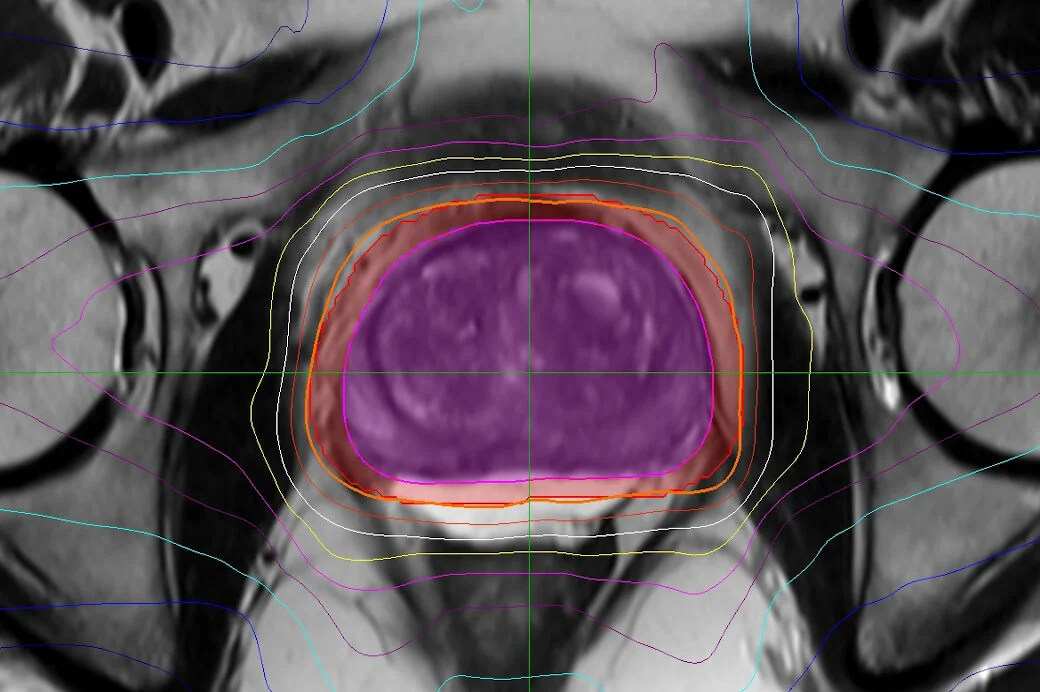

Contouring, Treatment Plan Evaluation, Fiducial and Hydrogel Assessment

contourtxprostate1.jpg